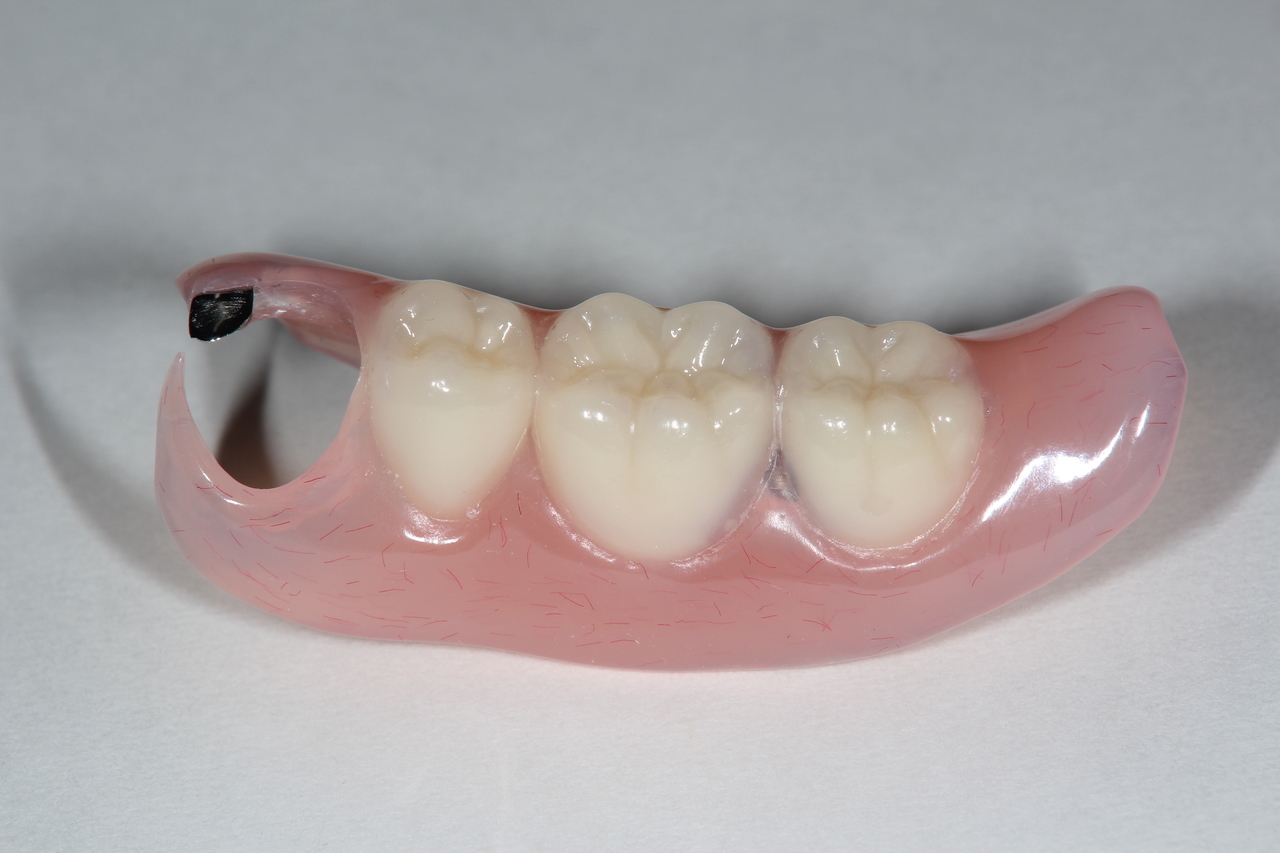

入れ歯

入れ歯装着前

入れ歯は一般的には歯を多く失った時に行う治療法で、型を取って、噛み合わせを記録して製作する取り外し可能な物です。保険で製作できますが、薄くて快適な入れ歯や、バネのないノンクラスプデンチャーは自費治療になります。

入れ歯は粘膜の上に乗せているだけなので噛むと沈み込み、土台の歯にバネの栓抜き効果が加わり、その歯が数年でダメになります。更に骨も経年と共に吸収していくので、合わない入れ歯を使用していると、更に悪化の速度が増します。

入れ歯の欠点

バネを掛けた歯は4年で90%に虫歯ができ、栓抜き効果で次々に歯が抜けてしまいます。最終的に総入れ歯になります。

入れ歯を付けている部分の顎の骨が1年間に0.5~1.0㎜ずつ痩せてしまうのです。だから、入れ歯は合わなくなるのです。